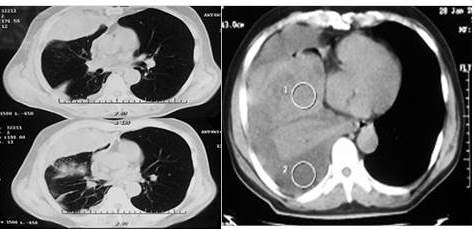

Debido al hallazgo de la radiografía se decide llevar a cabo un procedimiento de toracentesis diagnóstica, la cual fue positiva para líquido pleural serohemático, extrayéndose 20 cm3 para su estudio citoquímico y citológico. El resultado de la citoquímico de dicho líquido se reporta como un exudado con una celularidad a predomino de células tipos linfocitos 73 %, se programa y se realiza biopsia pleural con aguja de Abrams más colocación de sonda torácica conectada, drenaje posterior a control radiológico se observa imagen de masa posible lesión tumoral que ocupa lóbulo inferior del pulmón derecho. Se realizó una tomografía computarizada de tórax de alta resolución con contraste intravenoso que reveló una lesión redondeada, homogénea de 33 mm x13,7 mm, que ocupa la base del pulmón derecho (Figura 6).

El reporte de histopatológico al examen microscópico: los cortes histológicos muestran una lesión neoplásica maligna de estirpe mesenquimática fusocelular con fondo mixoide, ameritando estudio inmunohistoquímico que reportó sarcoma primario de pulmón monofásico (Figura 7 y 8)